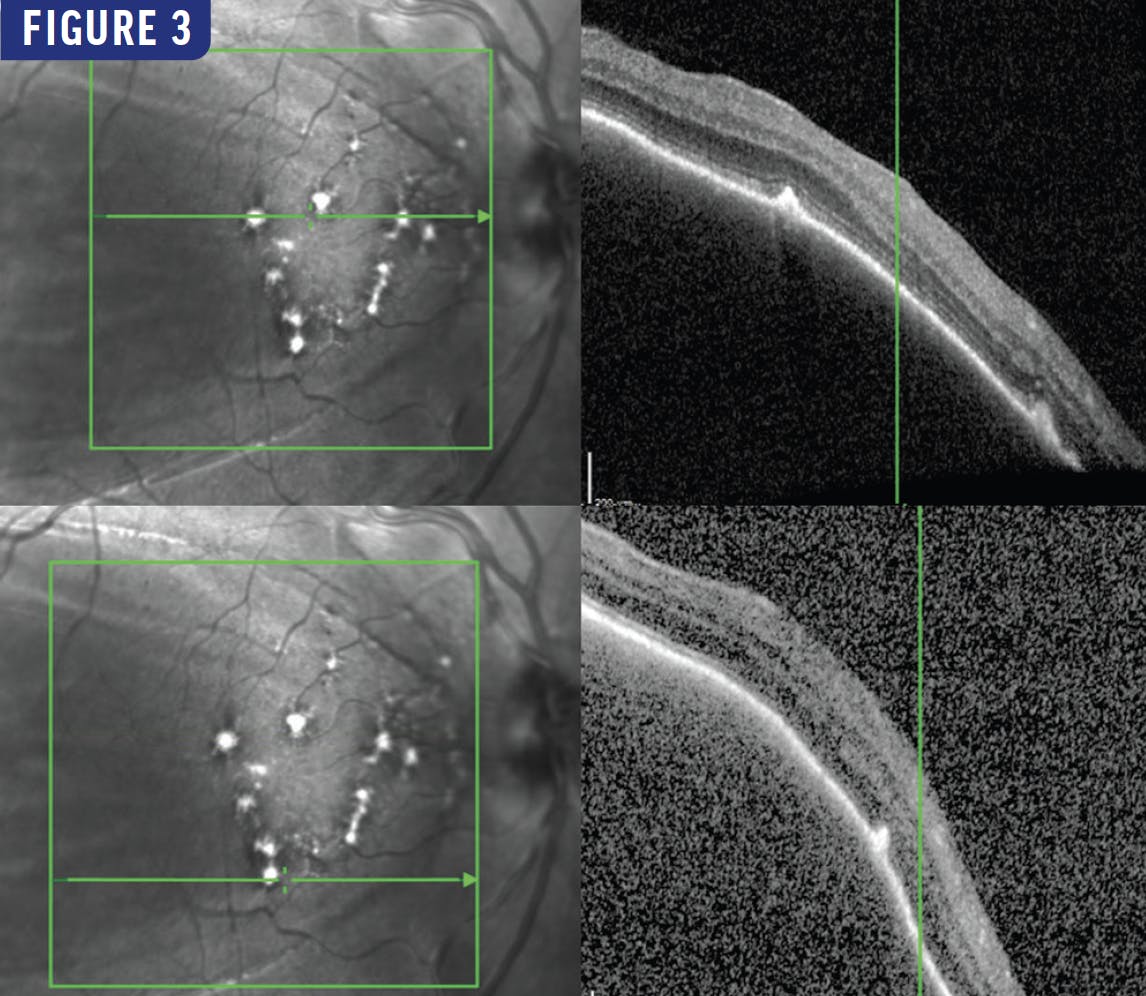

ICG angiography showed hypofluorescence corresponding to the choroidal lesions in the right eye. Fluorescein angiography showed early peripapillary blockage with late staining of the lesion in the right eye (Figure 2). Macular OCT showed choroidal elevation with an intact overlying retina and scattered subretinal hyperreflective lesions (Figure 3). B-scan ultrasonography showed peripapillary fundus thickening (Figure 4).